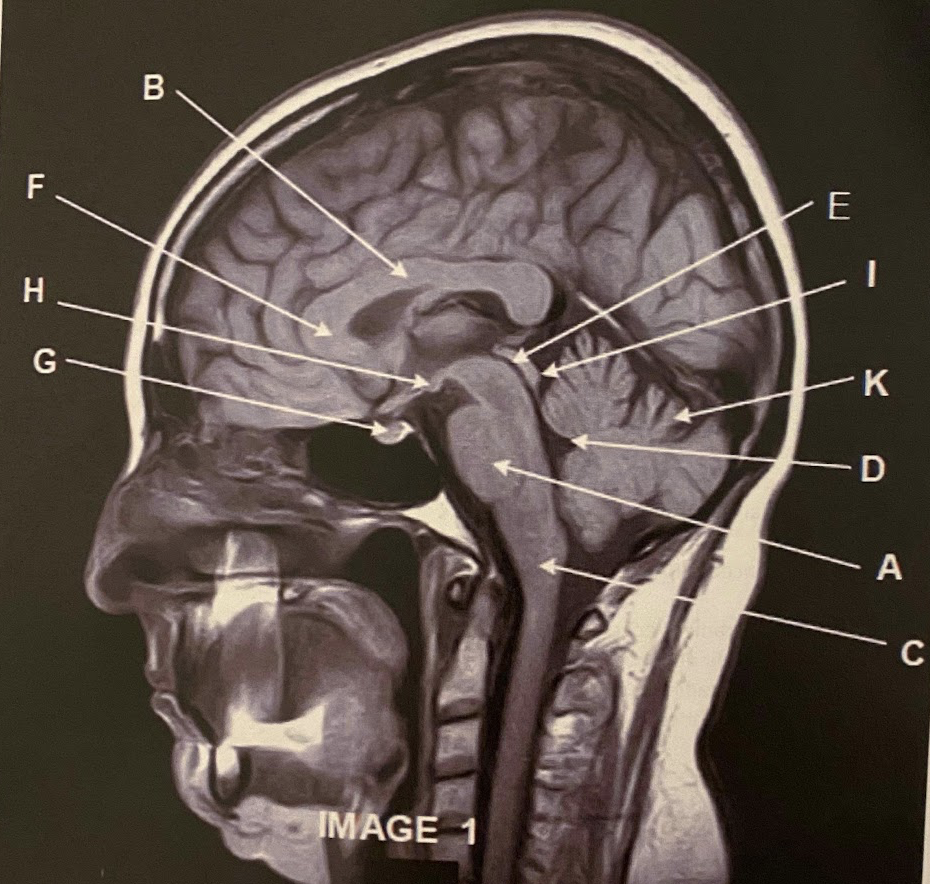

Q

The sagittal scan, demonstrates typical hyper intense tendril-like projections in the corpus callous characteristically seen in patients with what disease?

A) Tuberous Sclerosis

B) Multiple Calcified Nodules

C) Multiple Sclerosis

A

What anatomy is letter A pointing to?

Pons

3

What anatomy is letter B pointing to?

Corpus Callosum

4

What anatomy is letter C pointing to?

5

What anatomy is letter D pointing to?

6

What anatomy is letter E pointing to?

Aqueduct of Sylvius

7

What anatomy is letter F pointing to?

Genu of the corpus callous

8

What anatomy is letter G pointing to?

Pituitary

9

What anatomy is letter H pointing to?

Mammillary Bodies

10

What anatomy is letter I pointing to?

Quadrigeminal plate

11

This image is non-contrasted. It was acquired using a _______ sequence

A) Proton Density

B) T1

C) FLAIR

D) GRE